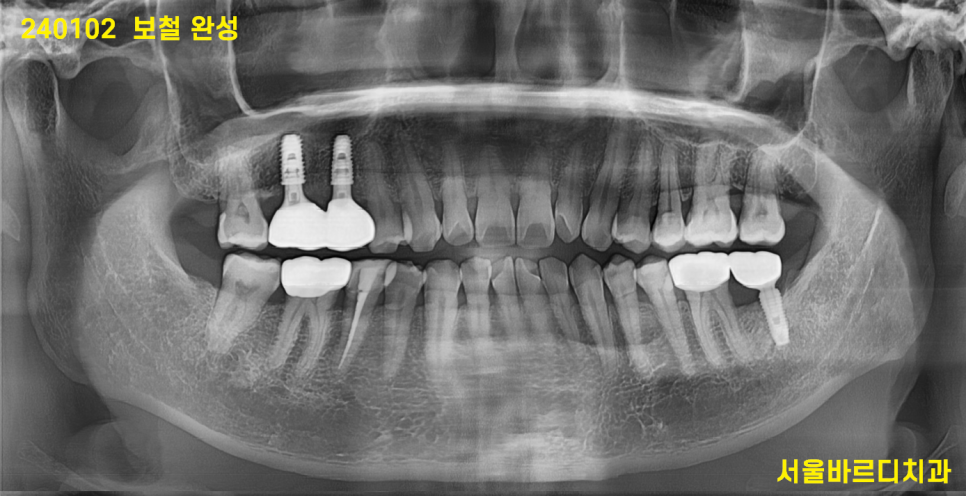

240102

9월달에 심고 이번에는 임플란트가

만들어놓은 뼈와 잘 붙어야합니다.

3개월을 추가적으로 기다렸습니다.

문제를 느끼고 치료한지 9개월이 지나

치아를 수복했네요.

빨간색 화살표가 임플란트 보철입니다.

너무나 자연스럽죠~?

환자분들께서는 임플란트 해 넣은 치아인지

전혀 모르실꺼같아

표시 한번 해보았습니다.

9개월이라는 대장정이었습니다.